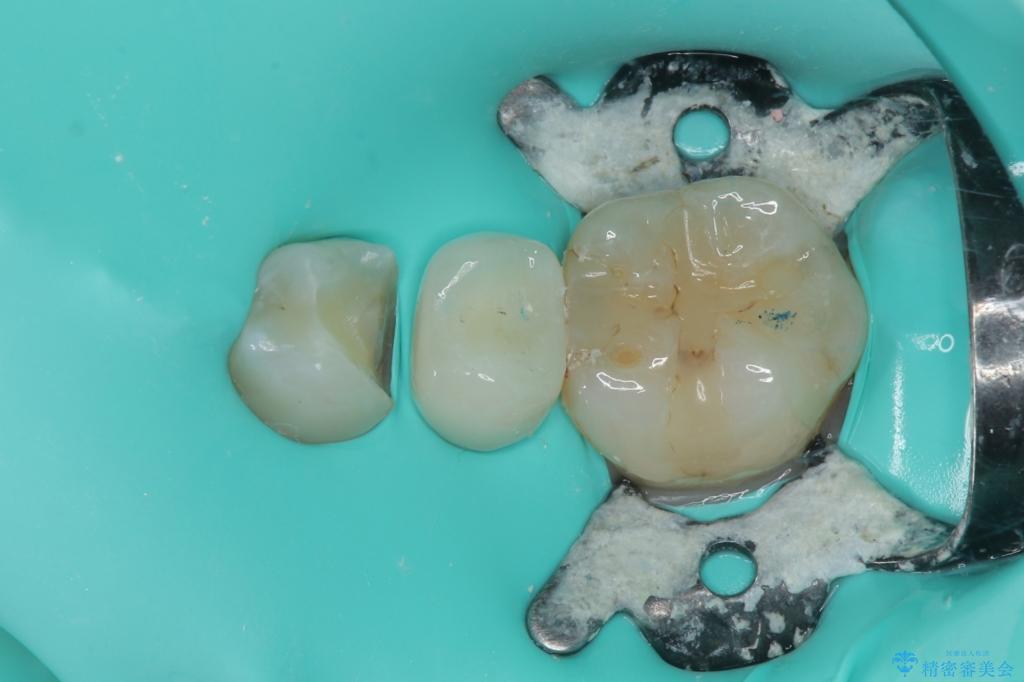

拡大鏡視野下で被せもの、虫歯の除去を行い、オールセラミッククラウン、セラミックインレーに適した形に整えました。

歯と歯茎の間に圧排糸と言われる糸を入れてシリコーン印象材にて精密な型どりをしました。

セラミックインレーの装着時には、唾液の侵入を防ぐために、ラバーダム防湿を行いました。